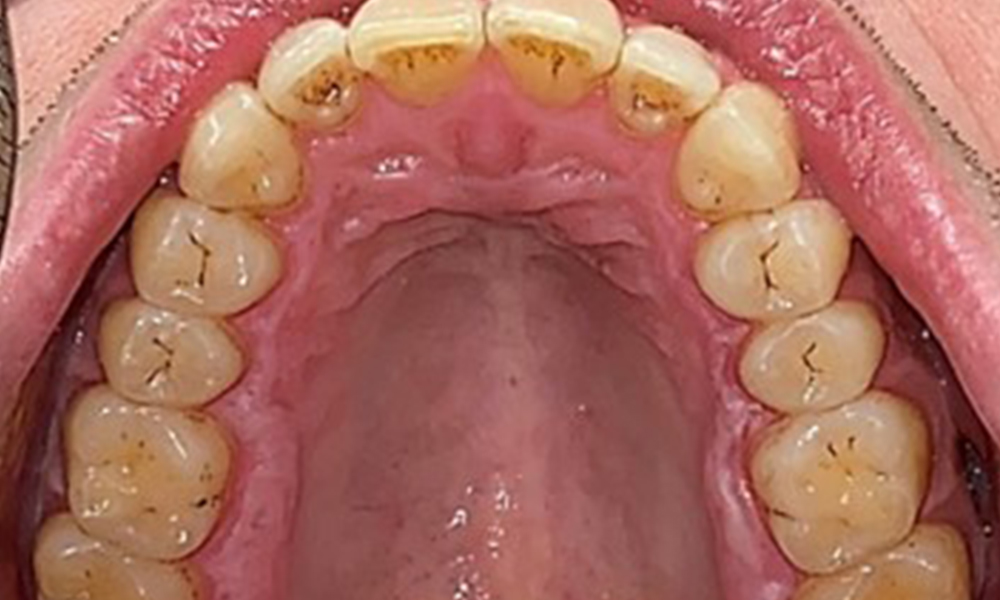

There were no pathological extraoral findings. During intraoral examination, inspection of the frontal view revealed brownish discolouration near the keratinised gingiva and at the transition to the moveable mucosa (Fig. 2), which could be attributed to nicotine consumption. Whitish mucosal lesions were observed on the palate, particularly near the maxillary molar palatal surfaces, indicating increased keratinisation and can also be attributed to nicotine consumption. The tongue was covered with a removable white and brownish coating.

The patient has full dentition with a total of 28 teeth. There were noteworthy erosions and attritions. (Fig. 4, Fig. 5). Due to bruxism, the patient has been wearing a splint with an adjusted bite block at night for many years. The erosions were caused by long-term consumption of isotonic beverages. No periodontal bone loss or active caries were observed.

Full complement of adult teeth with no caries or radiologically recognizable bone loss was observed (Fig. 6). Radiological enamel and cusp loss were particularly evident on 36 and 37.

Instruction and motivation are important components of these appointments. Good home-based intraoral hygiene behaviour and understanding are important for patients. Plaque accumulation is particularly evident in the cervical regions (Fig. 8).